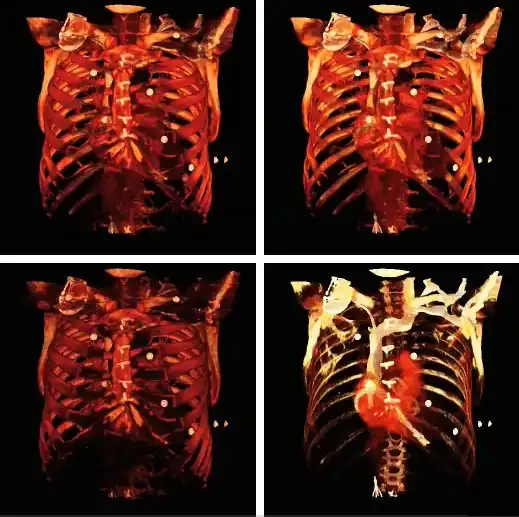

Volume rendering can be applied to the voxel data in the successive rotation manner described for MIPs above, as illustrated by the results in the following figure:

Note that the volume rendering can be contrast enhanced so as to threshold, for instance, through the voxel values to eliminate low attenuating surfaces, as illustrated in the following figure:

Note also that the colour look-up table (CLUT) can be varied to highlight features of particular interest, as shown in the set of images below:

The influence of the opacity table is illustrated in the following example images:

The influence on volume rendering of various shading settings is shown below:

The shading settings used for the above images are as follows:

| Image | Ambient Coefficient | Diffuse Coefficient | Specular Coefficient | Specular Power |

|---|---|---|---|---|

| Top Left | 0.15

|

0.9

0.3

15.0

| Top Middle | 0.75

| Top Right | 0.15

0.1

| Bottom Left | 0.15

1.2

| Bottom Middle | 0.15

1.0

| Bottom Right | 0.15

0.6

A final feature to note about volume rendering is that 3D editing techniques can be applied so as to exclude unwanted features from the computations and to expose internal structure. This is illustrated in the following figure, where planes of an orthogonal frame can be moved to crop the voxel data from six directions.